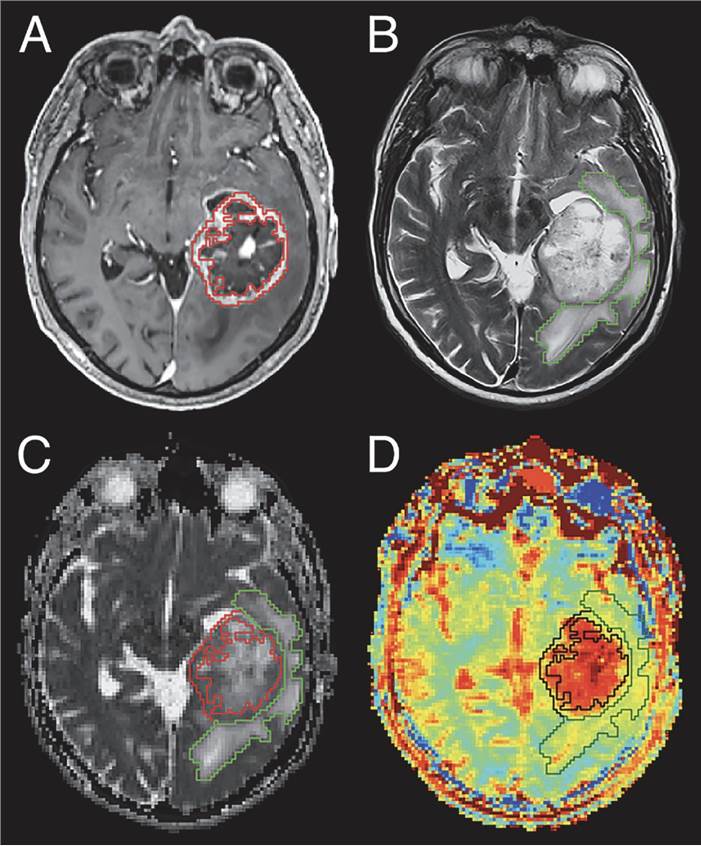

Contrast-Enhanced MRI Imaging in Glioblastoma. Fig.1 Contrast-Enhanced MRI Imaging in Glioblastoma.1,3

As a result, Creative Biolabs provides a panel of CE-MRI services that utilize novel contrast agents, higher field intensity Settings, and clearer time-resolved imaging to improve the spatial and temporal resolution and quality of conventional images, further increasing the sensitivity of detection of smaller metastatic lesions. For instance, based on the principle of increased tumor blood vessel distribution, our functional MRI platforms, such as perfusion imaging services, are gradually being used for brain tumor imaging. Among them, the rCBV threshold, all passage time, peak enhancement time, and other parameters on CE-MRI play a decisive role.